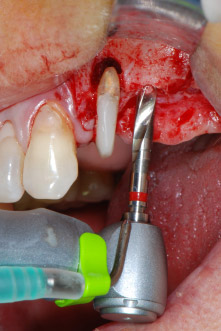

Имплантологичното ложе е подготвено в позиции 25 и 26 с ротиращи инструменти, използвайки обратен наконечник 20:1 с усъвършенстван и мощен имплантологичен мотор (Implantmed, W&H) (Фиг. 8).

Следващата препарация близо до синуса отново е извършена с пиезохирургичен накрайник (Piezomed, накрайник S2).

Фиг. 8: Препарация на имплантологичното ложе близо до пода на максиларния синус в позиция 25, изпълнена с новия имплантологичен мотор.